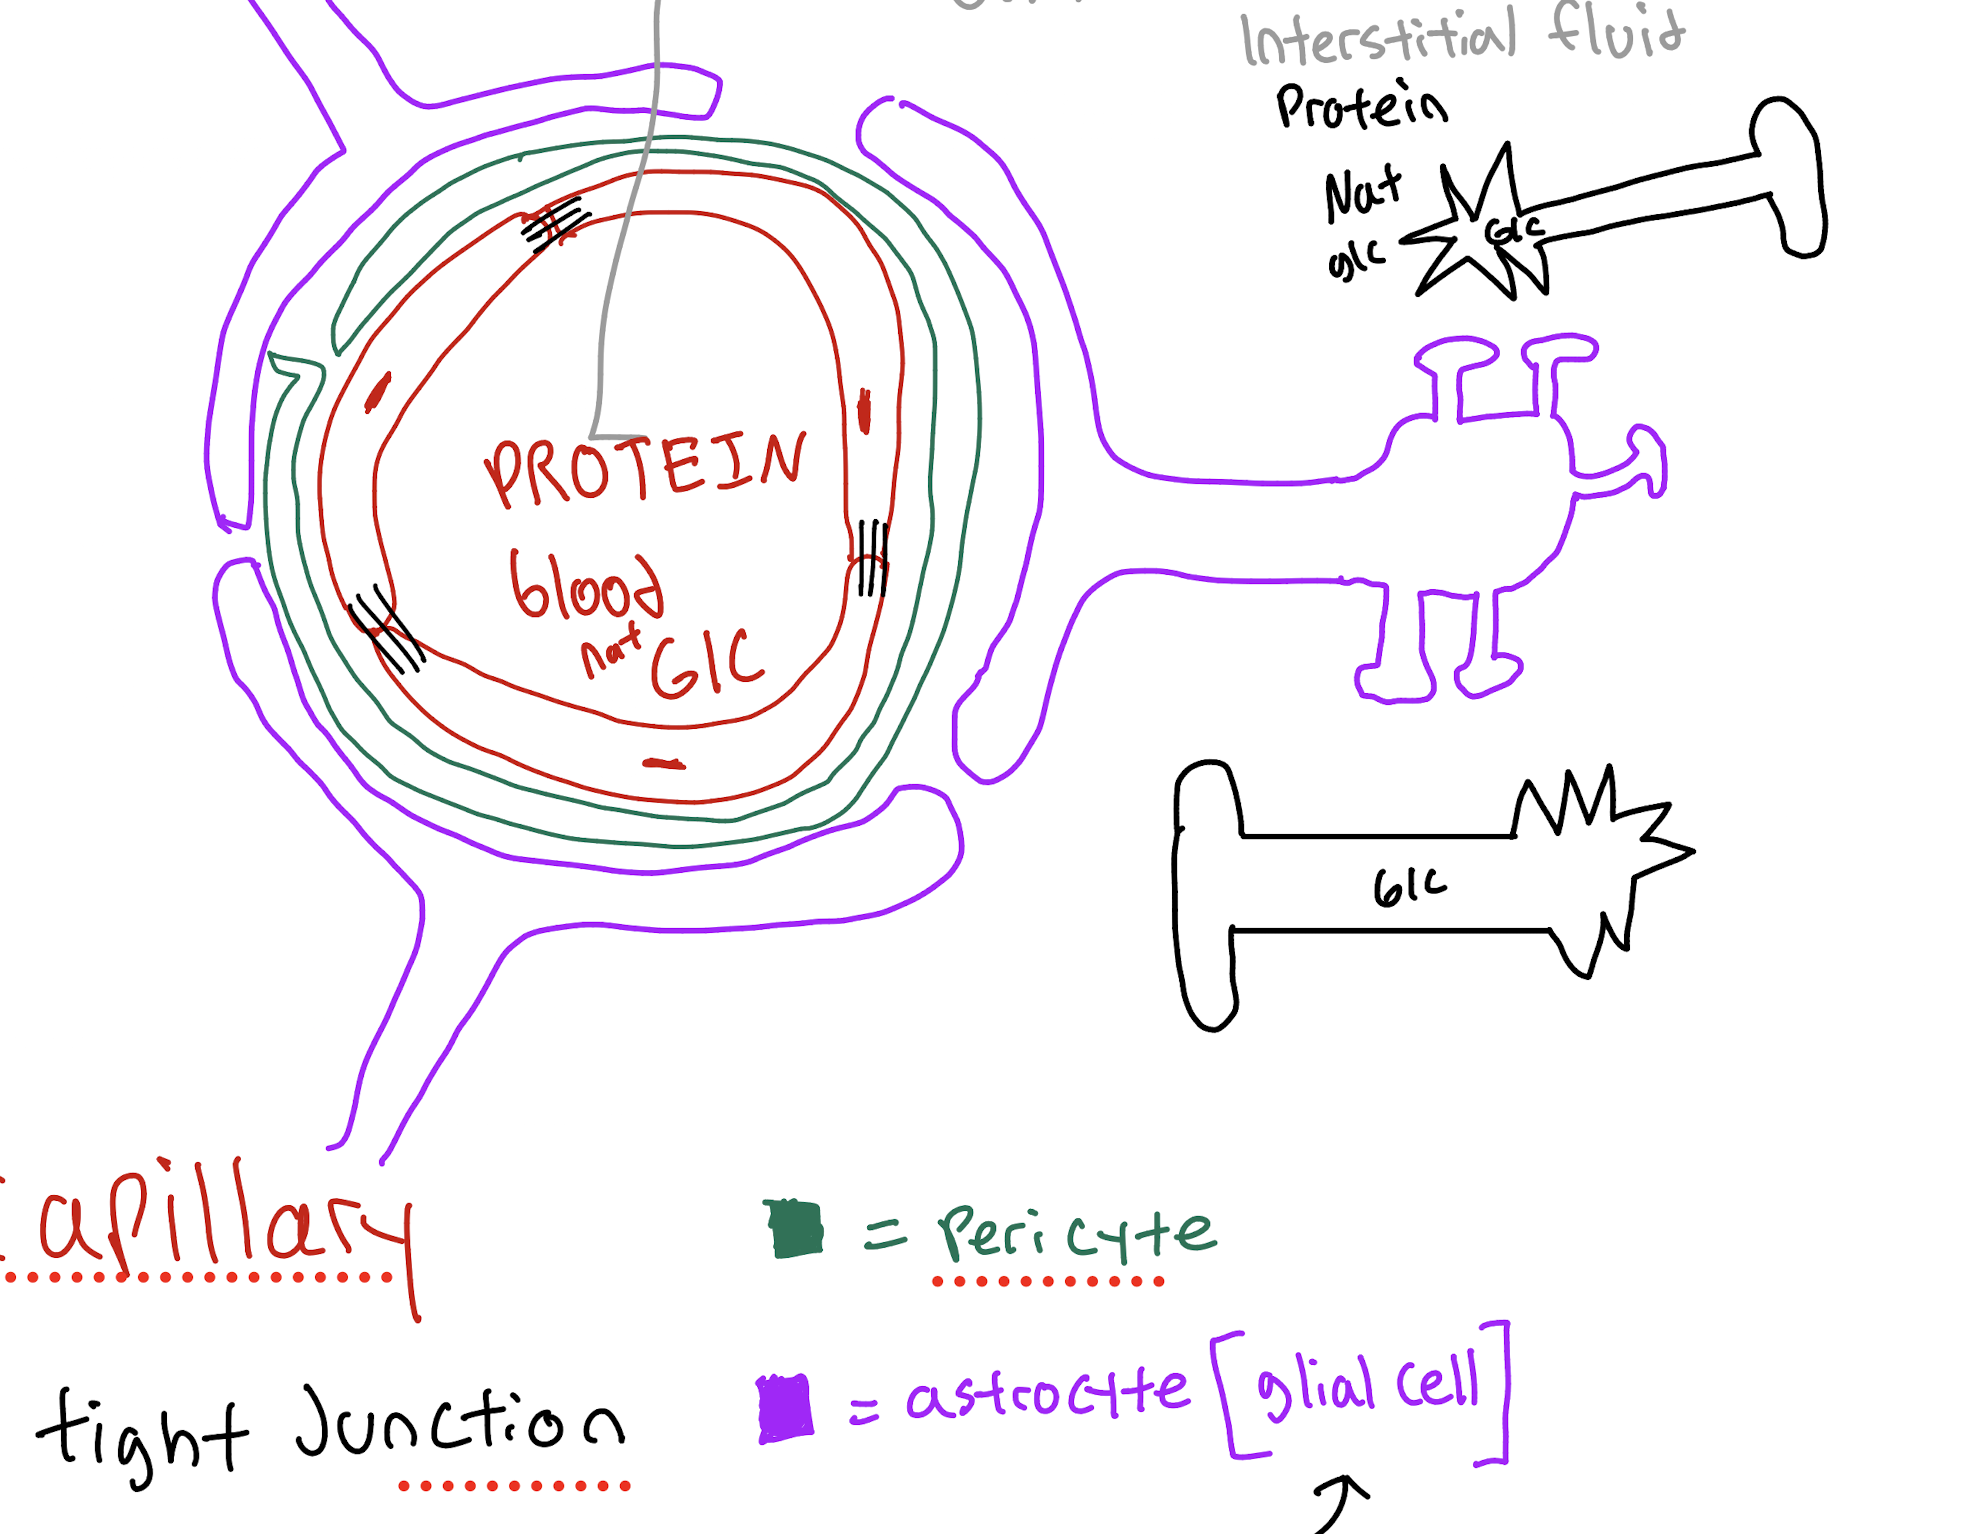

What Three cells/Structures make up the Neuromuscular unit (BBB)

(1) capillary endothelium

(2) pericyte

(3) astrocyte

What is the role of the capillary endothelium in the BBB

The main physical barrier that prevents protein,virus and bacteria from getting into the brain

What is the role of the pericyte in the BBB

Strengthens and controls vessel function (stabilizer)

What is the role of the Astrocyte in the BBB?

Does regulation of blood and supports it (Caretaker)

Why does the brain maintain a low-protein environment?

To limit cell proliferation (stop cell growth and spreading)

What is the primary source of energy for the brain?

Glucose (consumes about half of the body's glucose)